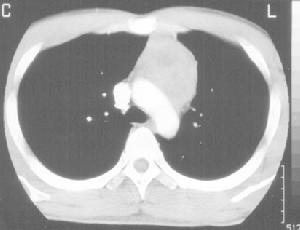

精原細胞瘤 後前位 側位20%-30%的病人無症狀,有症狀的病人症狀為胸痛、咳嗽、呼吸困難、咯血等,可以有嗜睡、體重減輕。10%~20%病人出現上腔靜脈梗阻綜合徵。這些臨床症狀常與腫瘤對縱隔結構的壓迫、侵犯有關。一部分精原細胞瘤生長在氣管內,並局部擴展至鄰近的縱隔和肺。一般縱隔精原細胞瘤經淋巴途徑轉移播散,亦可發生血行轉移,骨骼和肺臟是最常轉移的部位。

胸片多見巨大前縱隔腫瘤,有時可以發現腫瘤沿氣管內生長。CT多為密度均勻的大包塊,50%可見胸內轉移或擴展超出前縱隔而不能手術。CT和MRI有助於確定腫瘤的範圍、對縱隔結構的侵犯情況。首次就診切除率低於25%。

應對所有患前縱隔腫瘤的年輕男性測定血α-FP、β-hCG水平。單純的精原細胞瘤幾乎均無AFP、hCG的升高,7%-10%有hCG升高,但常不超過100ng/ml,AFP不升高。

CA125也可能為生物學標記。腫瘤組織的染色體分析可發現12號染色體上特徵性等臂染色體,這對鑑別生殖細胞腫瘤和其他類型的腫瘤有助。